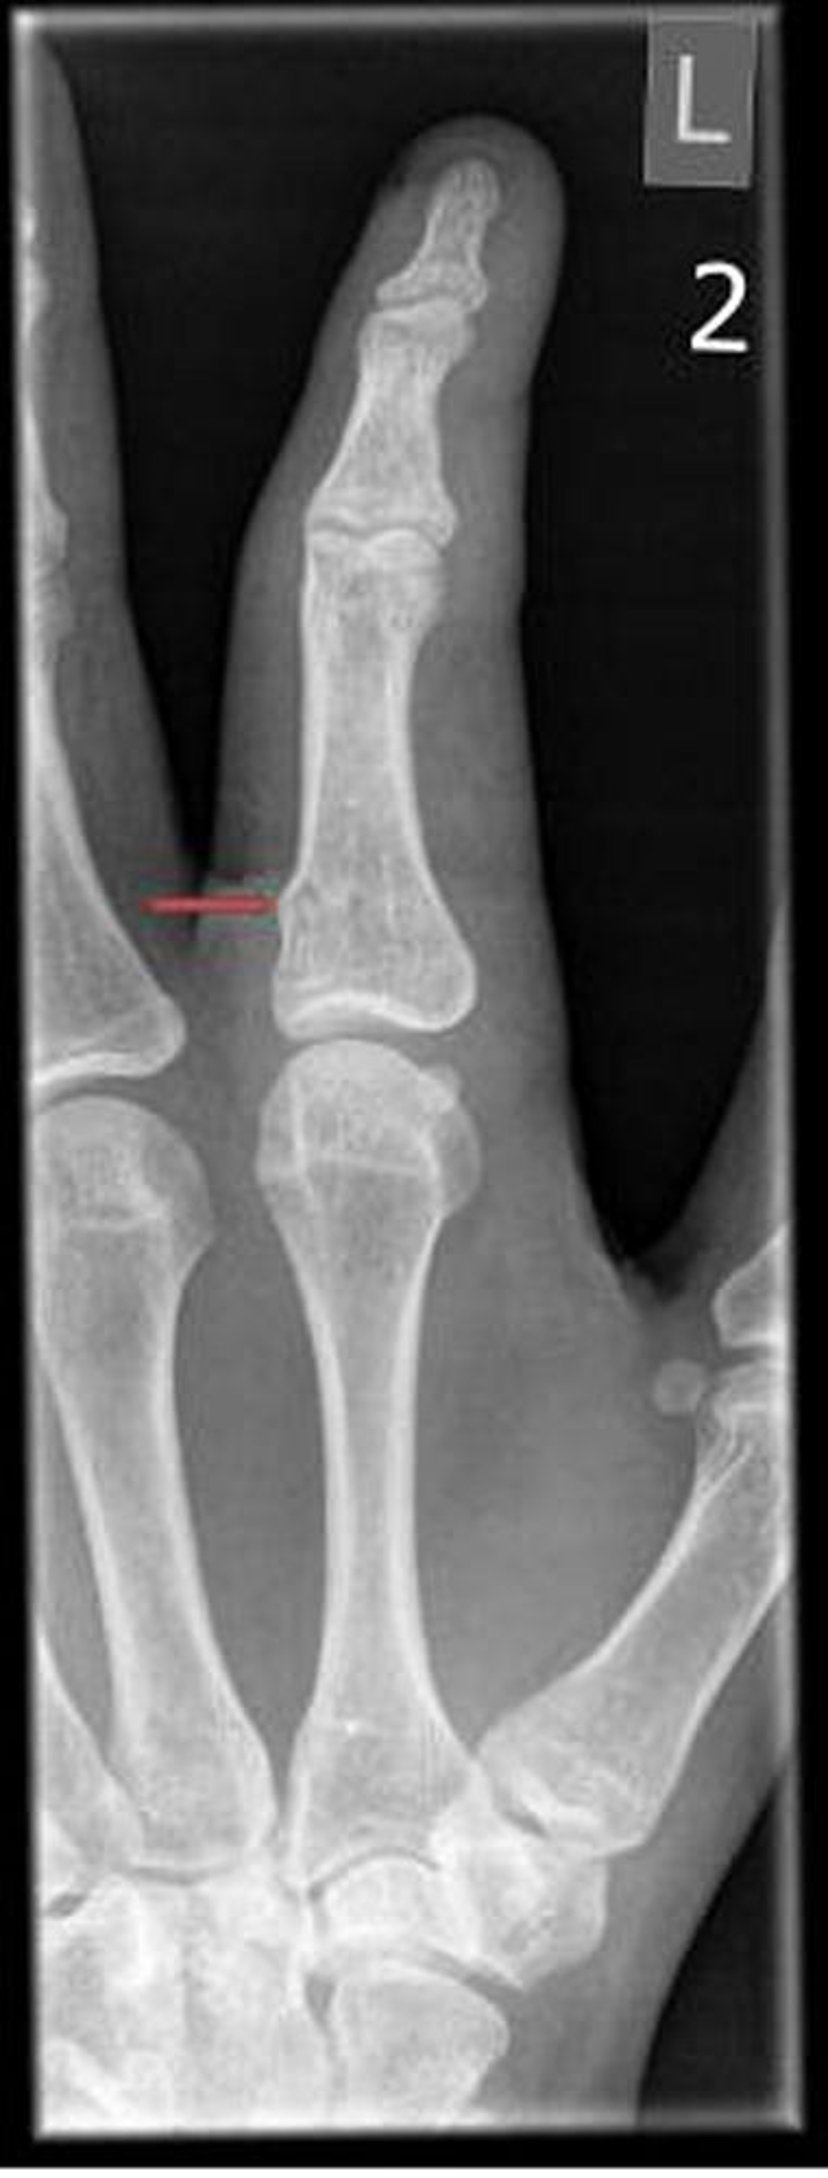

Fractura en rodete (de torus) del dedo

Las fracturas del rodete (torus) solo pueden evidenciarse como sutiles irregularidades en la corteza ósea.